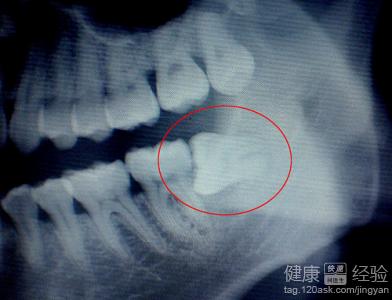

3還有就是有很多人雖然知道智齒的危害和必須拔除的道理,但是因怕疼遲遲不願趣治療,其實擔心拔牙疼是沒有必要的,不拔的話更會發生反復疼痛。拔牙前通過拍片,確定智齒的具體方向和位置,在根據患者的情況進行治療。